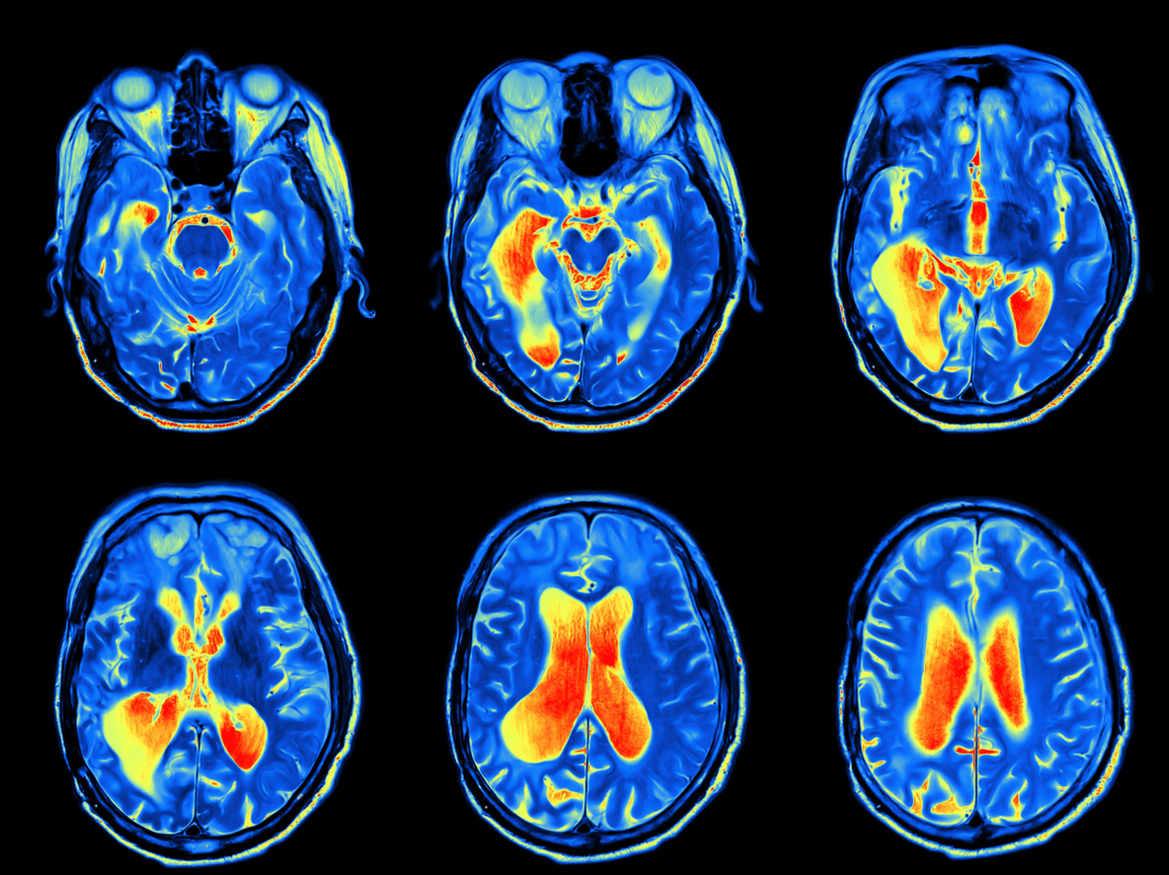

Ce sont les astrocytes, des cellules du système nerveux, et non les neurones qui sont à l’origine des signaux métaboliques utilisés en imagerie cérébrale.

Cette hypothèse, formulée il y a vingt ans par Luc Pellerin, vient d'être validée par le professeur de la Faculté de biologie et de médecine de l'Université de Lausanne. Cette étude pourrait, à terme, changer la détection et le traitement des maladies neurodégénératives comme Alzheimer ou Parkinson.